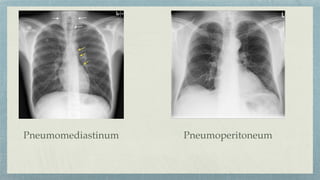

Pneumomediastinum Pneumoperitoneum